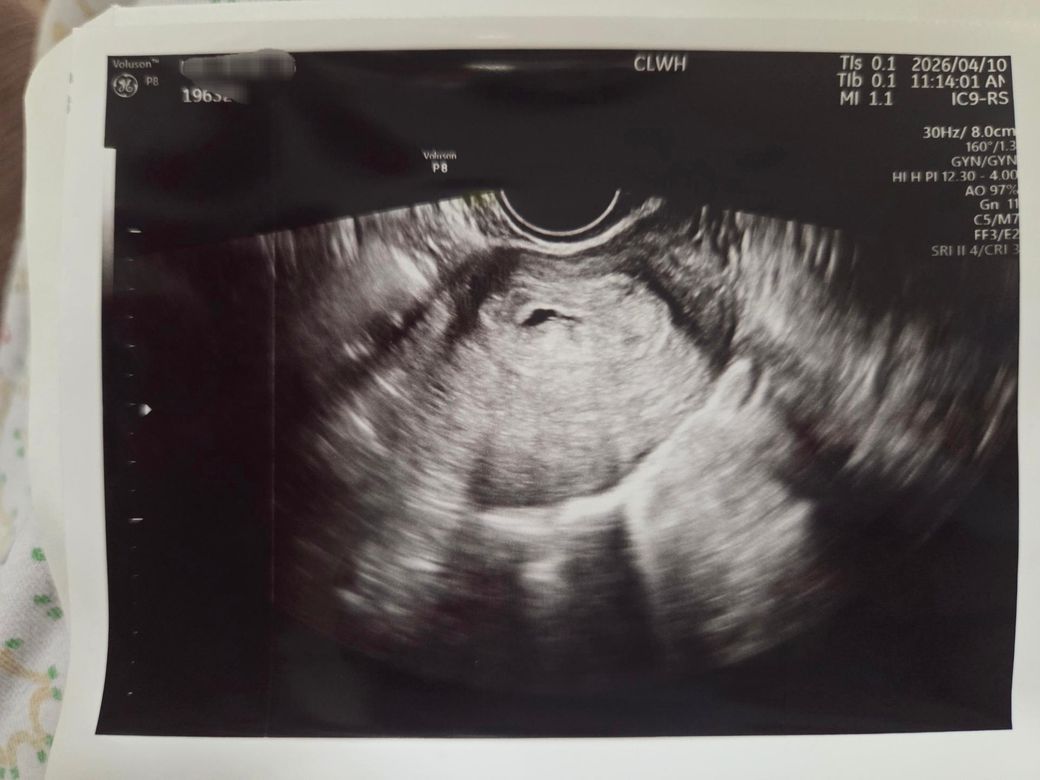

• 1번 째 사진

• 현재 상황은 정상 임신 진행과 초기 임신 실패 가능성이 함께 존재하는 경계 단계로 해석됩니다. 주수 차이 2일 정도는 초기 초음파에서는 흔한 오차 범위로 임상적 의미는 거의 없습니다.

임신 5주 중반에서는 보통 임신낭과 난황이 보이고, 5주 후반에서 6주 사이에 심박이 확인되기 시작합니다. 아직 심박이 보이지 않는 것 자체는 이 시기에서는 정상일 수 있으나, 이후 추적에서 나타나는지가 중요합니다.

초음파 사진 속 아기집이 아주 예쁘게 자리를 잘 잡은 것으로 보여요.

지금은 아기집의 크기와 위치를 확인하는 단계이며 심장 소리는 조금 더 시간이 지나야 들릴 수 있답니다.